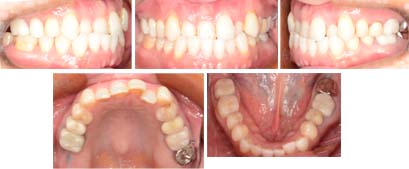

来院時の写真

気になっている点(主訴): 反対咬合 下顎前突

前歯部反対咬合です。すでに上顎右側第二大臼歯は失っています。また臼歯部には保険外の高額なセラミックなどで白く被せてあります。こういった白い保険外の歯には接着できません。変色しないとても硬い材質でできています。しかし、矯正治療できないわけではありません。色々な工夫することで治療は可能です。今回は非抜歯で限局的にリンガルブラケットを接着する事によってよい結果を得ました。